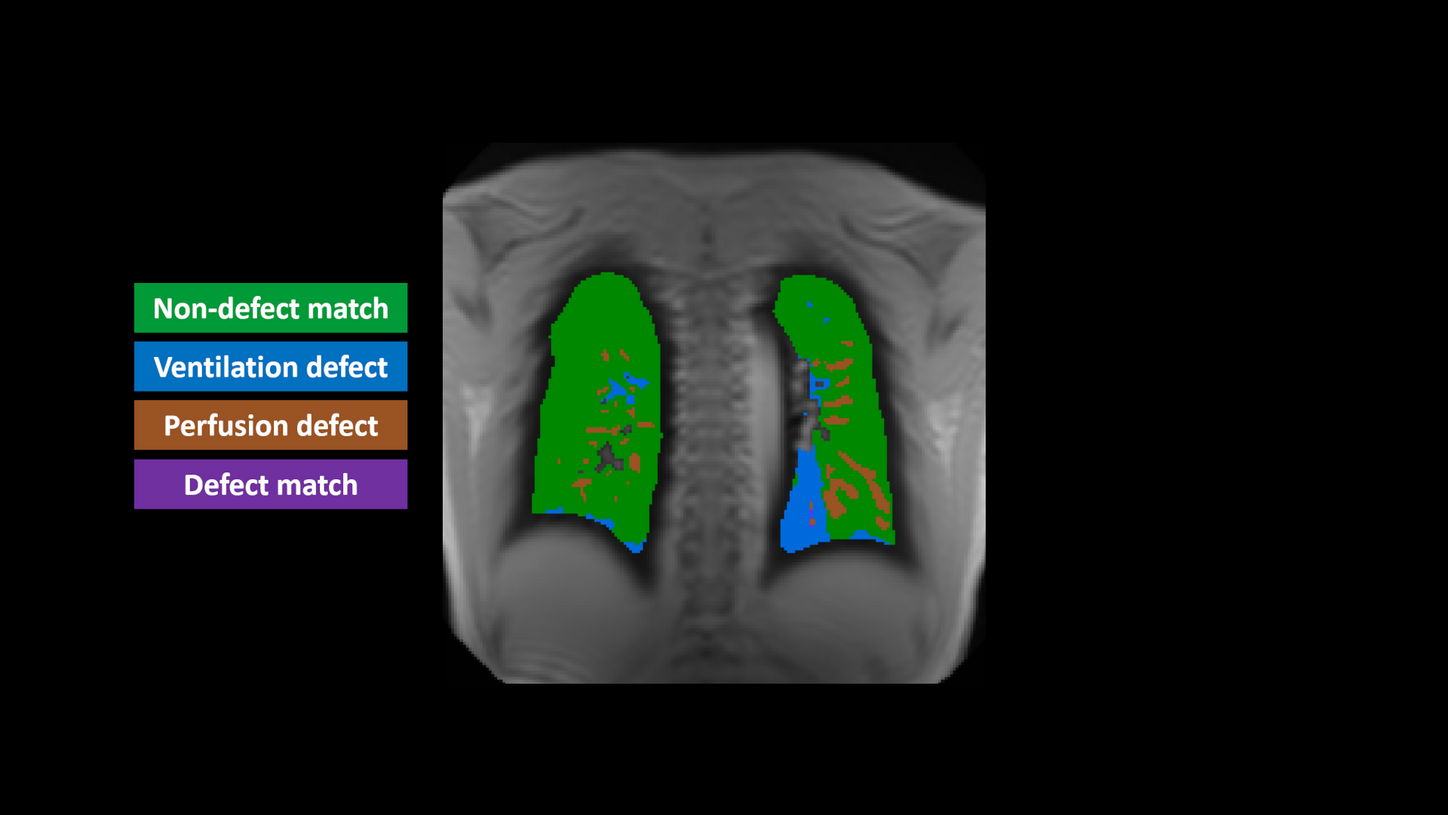

MAGNETOM Sola, Vw/Qw defect map | Study-ID: 1aaaa5517

LungMaps1

Besides morphology, information about ventilation and perfusion of the lung is critical to comprehensively assess lung diseases. Functional lung imaging without contrast agents marks a major step forward for follow-up imaging of chronic lung diseases such as cystic fibrosis (CF), chronic obstructive pulmonary disease (COPD) or chronic thromboembolic pulmonary hypertension (CTEPH). LungMaps results in ventilation- and perfusion-weighted maps of the lungs, without any radiation burden.

Your benefits:

- Free-breathing functional lung MRI without the need for additional equipment or tracers

- Automatic generation of meaningful information without the need for time-consuming manual interaction

- Perfectly suited for vulnerable groups such as children2 or pregnant women